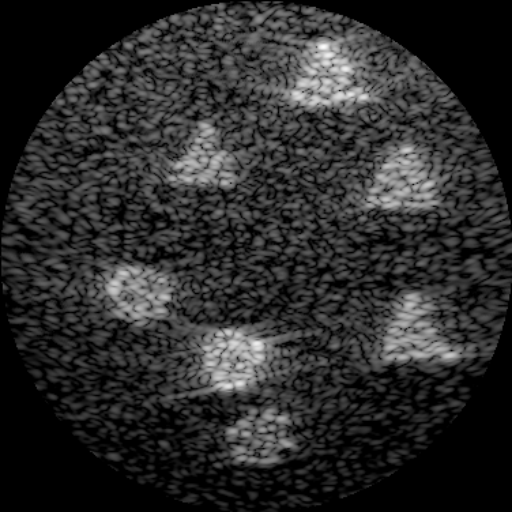

To tackle this, our approach also leverages the low-rank prior: the clean tissue is assumed to lie on a low-rank subspace, while speckle noise is more prominently expressed in the high-rank or sparse components. To enable implicit separation of these components from just a single noisy observation , we design a transformation called multi-scale perturbation (MSP), denoted as , where indicates the perturbation scale. MSP applies controlled downsampling–upsampling operations to generate multiple perturbed versions of the same noisy B-mode image :

| (7) |

Specifically, this operation first downsamples the image by a factor of in both spatial dimensions (i.e., scaling the width and height by ), then upsamples it back to the original image size. The generated variants preserve the same anatomical structure , while exhibiting different speckle patterns due to the scale-dependent distortions introduced by . As illustrated in Fig. 4, after applying MSP, the boundaries of the thyroid remain visually consistent across different scales, while the speckle patterns in the homogeneous thyroid region vary significantly across the perturbed versions—effectively forming multiple images that share the same low-rank content but differ in speckle characteristics for the same scene. In our implementation, we use three scale factors , corresponding to , where each input is first downsampled by and then upsampled back to the original resolution.

To investigate whether the MSP is able to introduce enough variation for the tissue speckle component, we perform a frequency-domain analysis on the three images after applying MSP with different scales. The low-rank tissue component is approximately extracted using the low-frequency bands, and the remaining high-frequency component is referred to as speckle. To this end, the Fourier transform (FFT) is applied to each variant (Fig. 3). Following [81], we isolate different frequency bands using the patch mask centered at the frequency image center, and reconstruct corresponding sub-images via inverse FFT. In Fig. 3, the low-rank part shows high consistency while the high frequency exhibits a certain variation. This finding is also supported by the following correlation analysis across scales. This demonstrates the MSP can generate variants with common low-rank content but distinct non-structural components, including speckle. This lays the foundation for the following tissue-dependent speckle reduction.